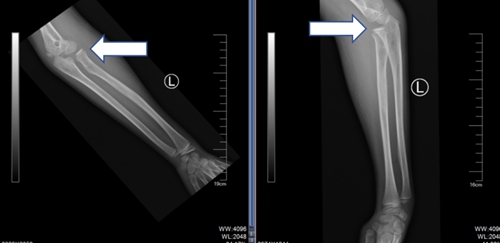

01 病例一

7 歲的皮皮(化名)周末在戶外玩耍時(shí),不慎摔傷左上肢,當(dāng)?shù)蒯t(yī)院診斷為左側(cè)孟氏骨折。醫(yī)生多次嘗試手法復(fù)位均未成功,孩子疼得直哭,家長(zhǎng)既心疼又焦慮。輾轉(zhuǎn)打聽后,他們帶著皮皮來到青島市婦女兒童醫(yī)院兒童骨折整復(fù)門診。讓家長(zhǎng)驚喜的是,醫(yī)生先耐心安撫了皮皮的情緒,隨后憑借精湛技術(shù),不到 3 分鐘就完成了手法復(fù)位。配合石膏固定后,皮皮的疼痛感立刻減輕,后經(jīng)過一段時(shí)間的恢復(fù),復(fù)查顯示骨折已完全復(fù)位。

復(fù)位前

復(fù)位后